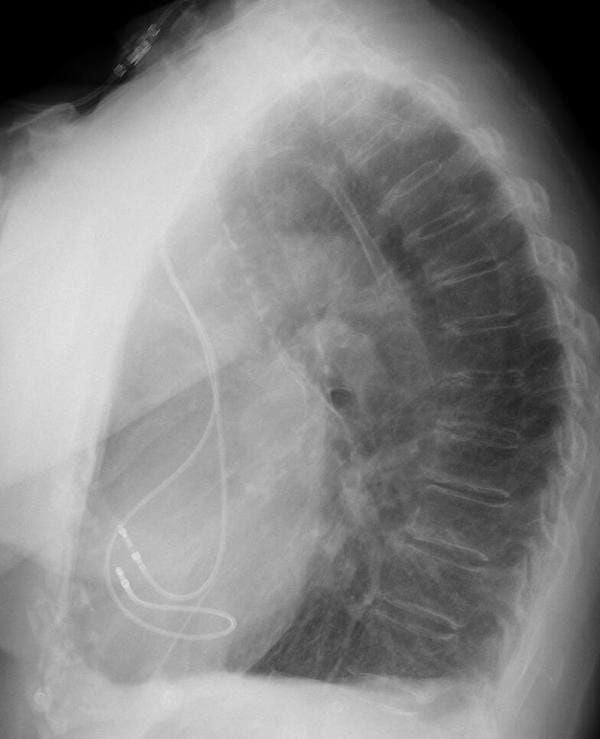

PA CXR INTERPRETATION

PA chest x-ray with appropriate penetration, exposure, with some rotation.

A dual chamber pacemaker is in-situ with atrial and ventricular leads noted, it is possible the ventricular lead crosses high, but overall position looks OK.

The right costophrenic angle is not fully visualised, but the left costophrenic angle is clear.

There is cardiomegaly with the cardiothoracic ratio ~0.6.

There is no visible pneumothorax.

There is an oblique artefact across the upper thorax likely either oxygen tubing or monitoring cable.

But we’re concerned about the lead position given our ECG findings and the PA CXR hasn’t really helped…